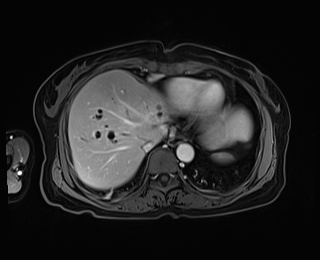

经知情同意后,2021年7月15日在局麻下行PTBD穿刺引流减黄,并于2021年8月2日行肿块活检术,术后病理结果为腺癌,经过减黄、营养支持、护肝等治疗后,患者全身各指标好转后于2021年8月12日开始实施化疗联合免疫治疗进行转化,经过7个月的转化治疗,复查肝胆增强磁共振示:右肝转移灶消失,肝门肿块缩小,同时进一步完善PET-CT,未见肿瘤全身扩散,局部与MRI一致,考虑肿瘤转化降期成功,而此时,患者免疫治疗相关药物不良反应开始出现,表现为皮疹、口腔溃疡等,再次经科内讨论,认为手术条件已经成熟,可以考虑手术治疗,术前完善三维可视化肝脏体积评估,残留左外叶占标准肝体积45.6%,符合指南肝切除预留肝体积指标。

转化治疗前 转化治疗后